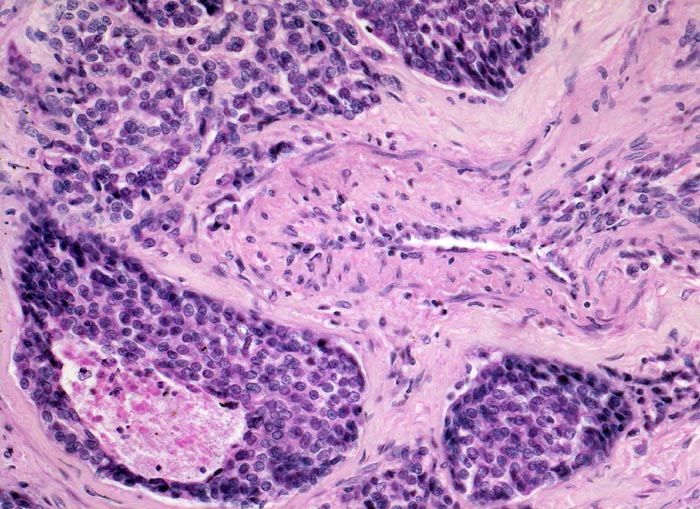

neuroendokrines Karzinom: Lymphangiosis carcinomatosa

Auffallend monomorphe, zytoplasmaarme Tumorzellen mit runden Kernen bilden solide scharf begrenzte Aggregate in Lymphgefässspalten rund um einen Pulmonalarterienast (Lymphangiosis carcinomatosa). Ein weiterer Tumorherd infiltriert das perivaskuläre Bindegewebe und ist entsprechend unscharf begrenzt. Tumornekrose.

Metastasierendes Tumorleiden bei unbekanntem Primärtumor. Autoptisch primäres peripheres neuroendokrines Karzinom der Lunge mit ausgedehnter lymphogener und hämatogener Metastasierung.

Obwohl keine sichere Lymphgefässwand identifiziert werden kann, ist aufgrund der Lage eines Teils der Tumorzellaggregate rund um einen Pulmonalarterienast und der scharfen Begrenzung anzunehmen, dass sich der Tumor in den dort lokalisierten Lymhspalten ausbreitet.